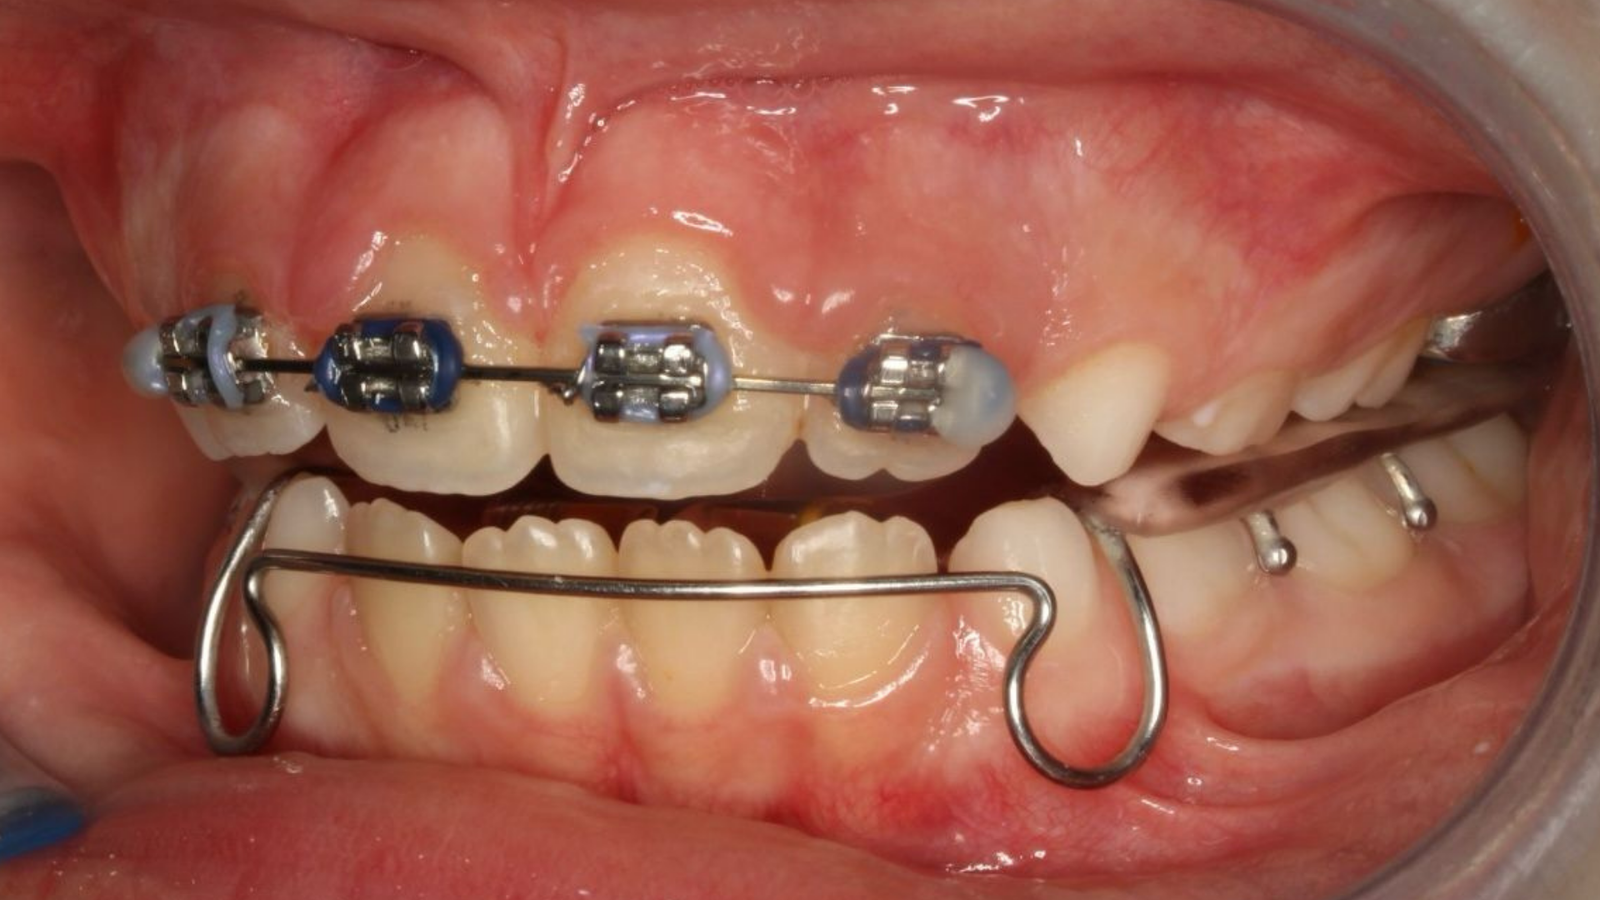

Cada paciente y cada tratamiento es único. El profundo conocimiento de la anatomía y de nuestros pacientes junto con la tecnología más avanzada nos permite realizar diagnósticos certeros. Localizando el origen del problema muchas veces incluso antes de que se produzca evitando así su aparición.

con ortopedia y ortodoncia, paso a paso.